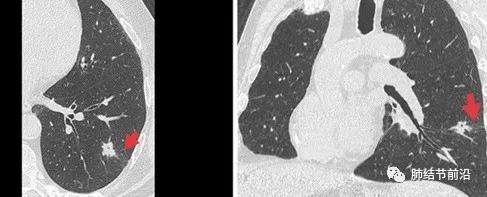

也有一些CT表现,可以间接预测STAS的可能。首先,STAS很少发生于磨玻璃结节,主要发生于实性或实性结节为主的肺结节。CT特征还有:结节有毛刺,有卫星灶,胸膜粘连,磨玻璃条带,以及不清晰的瘤-肺边界。

STAS显示为结节外侧的磨玻璃条带。

STAS显示为肺结节非常规的相邻双中心生长